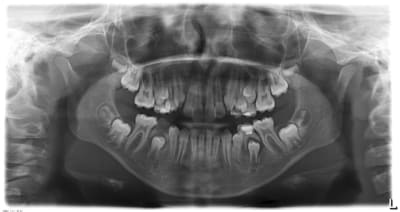

Le cas de conscience: la même orthodontiste veut baguer le petit frère de ma patiente. Son hygiène est aussi nulle que celle de sa soeur. Il a 9 ans. Je vous met la pano du frangin. Le problème d'encombrement (peu important) ne me parait vraimenet pas primordial au vue des risques carieux